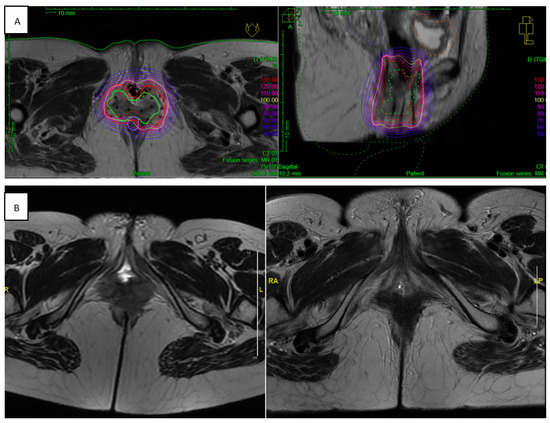

3.3. BT Specification

3.3.1. Implantation Procedure

3.3.2. BT Technique

3.3.3. Treatment Planning Modalities

3.3.4. Target Delineation

3.3.5. Dose Constraints